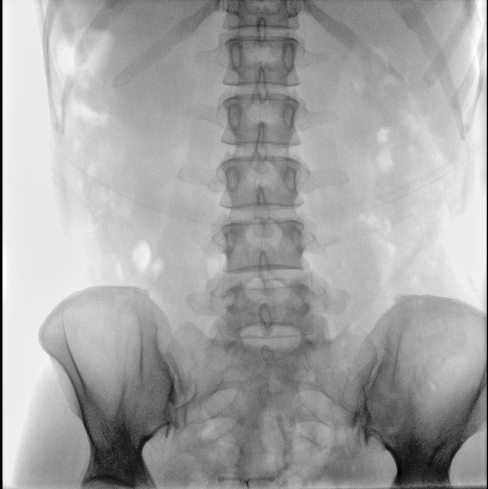

平板尺寸升級 呈現(xiàn)更多解剖細節(jié)

采用30CM×30CM大尺寸動態(tài)平板探測器,成像面積較傳統(tǒng)平板探測器大幅提升。

圖像清晰細膩

高清像素,低信噪比,細小的組織結構也可以清晰顯示。

Clinical picture

臨床圖片